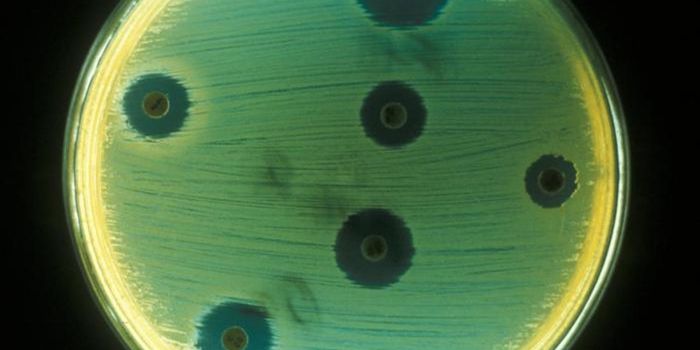

APR 20, 2022ImmunologyAntibiotic resistance has increased the demand for new antibiotic treatments. Now, researchers have found that a ...

APR 10, 2022MicrobiologyThere is growing concern about whether our antibiotics can keep pace with the threats posed by new and emerging bacteria ...

MAR 22, 2022MicrobiologyAlthough antibiotic resistance is becoming a problem, many bacterial infections can still be prevented or eliminated wit ...

MAR 09, 2022MicrobiologyAntibiotic resistance is already a major threat to public health; in 2019 alone, antibiotic resistant bacterial infectio ...

JAN 22, 2022MicrobiologyAntibiotic-resistant infections pose a serious threat to human health, which is expected to get worse. Bacterial infecti ...

OCT 05, 2021MicrobiologyAntibiotic resistance is seen as a growing threat to public health, and scientists have been trying to develop new antib ...